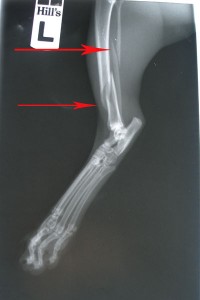

Rentgeny zlomené kosti holení a lýtkové